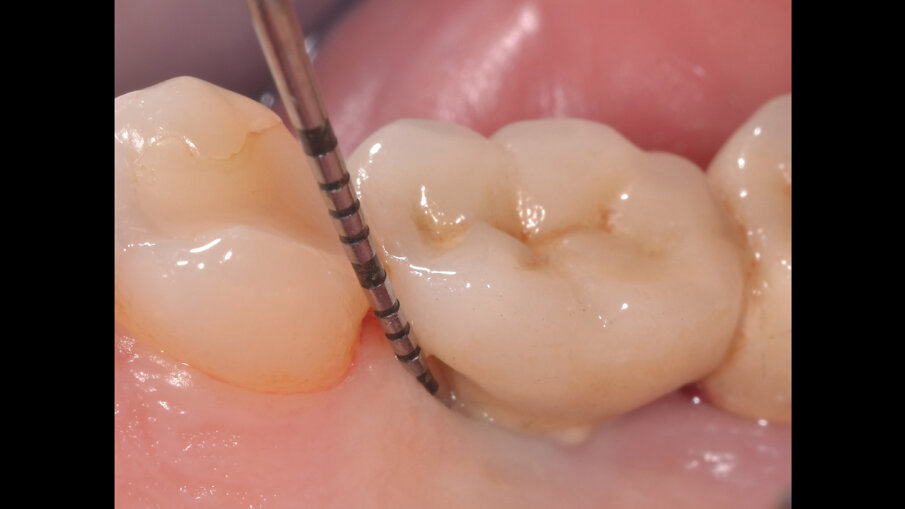

Il paziente, di sesso maschile e di 48 anni di età, è in buone condizioni di salute generale ma, a distanza di 10 anni dall’inserimento, presenta due impianti endossei, in posizione 4.6 e 4.7 con uniforme perdita ossea e con sondaggi di profondità variabile tra 6 e 9 mm accompagnati da sanguinamento, con tessuti marginali che mostrano importanti aspetti infiammatori, causa di sintomatologia dolorosa per il paziente (Figg. 1a-f).

I siti interessati sono stati strumentati per via non chirurgica, utilizzando strumenti manuali, strumenti ultrasonici e air polishing con eritritolo. Al termine della seduta è stato applicato il gel di ozono (Ozosan Gel - Bioactiva) all’interno delle tasche, lasciando agire il dispositivo per 8 minuti, quindi eseguendo lavaggio con soluzione fisiologica. Il post-operatorio ha avuto un decorso privo di dolore con rapida remissione della sintomatologia soggettiva. Il paziente è stato inserito in un programma di mantenimento parodontale trimestrale. A distanza di 6 mesi dal trattamento non chirurgico della perimplantite, i siti si presentano stabili con profondità di sondaggio ridotta tra i 3 e i 5 mm con assenza completa di sanguinamento al sondaggio (Figg. 1g-m).